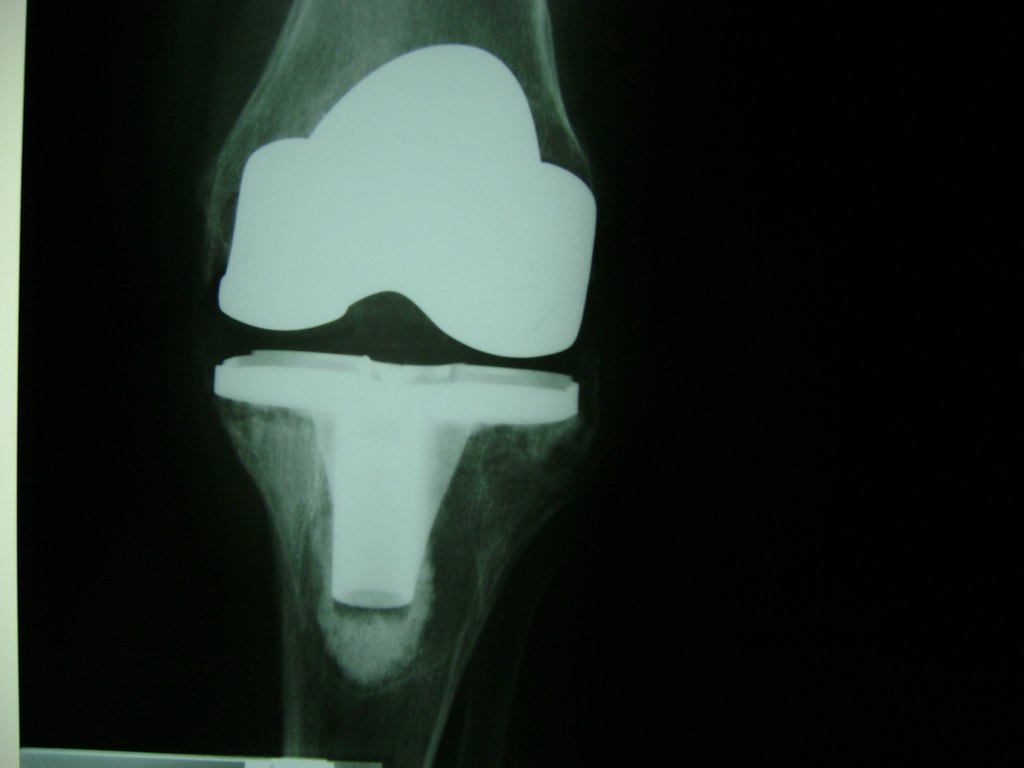

Cirugía de Fémur - Rodilla